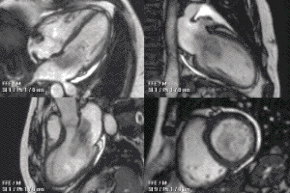

A CMR study typically comprises a set of sequences in a protocol tailored to the specific indication for the exam.[20] A study begins with localisers to assist with image planning, and then a set of retrospectively-gated cine sequences to assess biventricular function in standard orientations. Contrast medium is given intravenously to assess myocardial perfusion and LGE. Phase contrast imaging may be used to quantify valvular regurgitant fraction and shunt volume. Additional sequences may include T1 and T2-weighted imaging and MR angiography. Examples are below:

Heart function using cine imaging

Functional and structural information is acquired using bSSFP cine sequences. These are usually retrospectively-gated and have intrinsically high contrast in cardiac imaging due to the relatively high T2:T1 ratio of blood compared to myocardium. Images are typically planned sequentially to achieve the standard cardiac planes used for assessment. Turbulent flow causes dephasing and signal loss allowing valvular disease to be qualitatively appreciated. The left ventricular short axis cines are acquired from base to apex and are used for quantifying end-diastolic and end-systolic volumes, as well as myocardial mass. Tagging sequences excite a grid pattern that deforms with cardiac contraction allowing strain to be assessed.